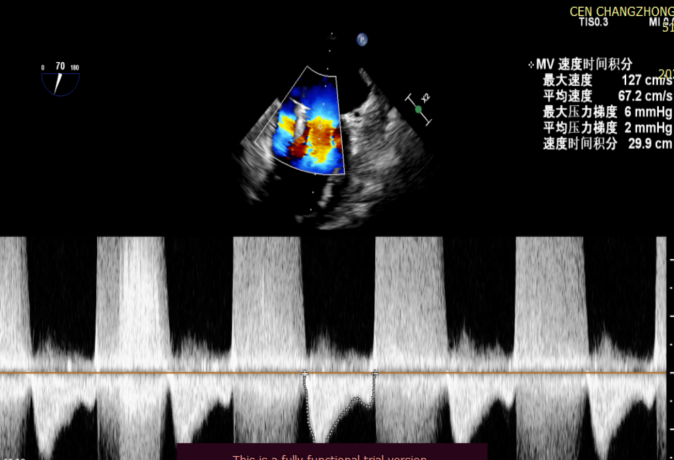

患者全麻后在超声和射线引导下穿刺股静脉-房间隔,器械顺利到达病变的二尖瓣区域,成功完成二尖瓣夹合后,患者二尖瓣反流即刻显著下降,左房压力即刻减低,预示着患者的临床症状将会得到明显改善。